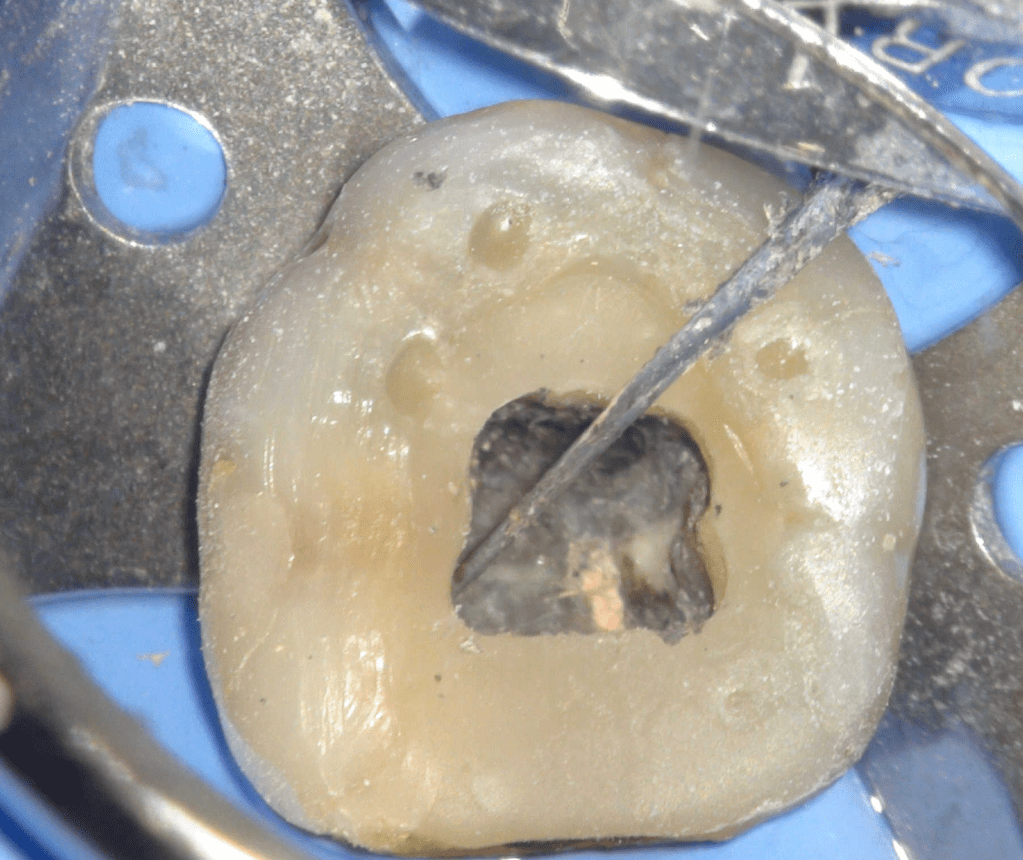

Fisura, remoción amalgama para explorar